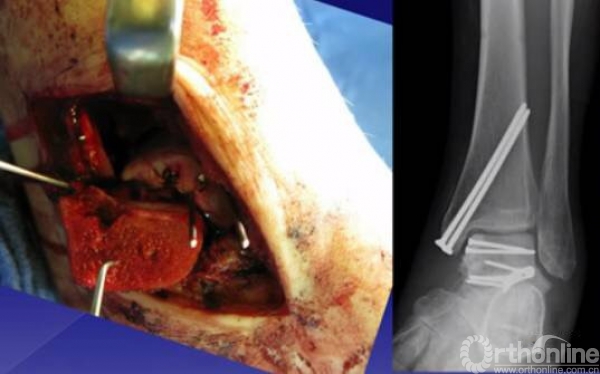

手术入路

1.内侧入路

比较安全,注意大隐静脉和隐神经

骨折十分粉碎时可采用内踝截骨,事先可进行螺钉的拧入,类似鹰嘴截骨。

2.外侧入路

如果一侧钢板的位置不佳,则容易造成另外一侧的骨折裂开。所以最好的固定是一侧用钢板固定,另外一侧可采用螺钉进行加压,对于颈部的骨折,避免另外一侧开口。